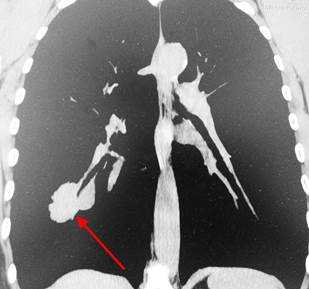

КТ-признаки туберкуломы легкого. Образование диаметром 2 см расположено в правом легком. Отличить туберкулому от рака помогает наличие глыбчатых кальцинатов (извести) в структуре образования, четкие контуры, окружающие фиброзные тяжи, а также мелкие очаги отсева вокруг.

Рентгенография при раке легкого выявляет округлую тень слева. С целью дифференциальной диагностики (отличить рак легкого от туберкуломы, кисты или пневмонии) необходимо выполнять компьютерную томографию — КТ.